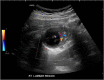

Duplication cysts are rare benign congenital malformations typically identified in children by the age of 2 years. We report a rare case of colonic duplication cyst with dysplasia in an adult. A 32-year-old male was diagnosed with non-specific abdominal symptoms. Abdominopelvic computed tomography scan demonstrated a submucosal cystic lesion in the right colon. He underwent laparoscopic right hemicolectomy. Histopathology showed colonic duplication cyst with low grade dysplasia. He is due for a surveillance colonoscopy in 3 years. Duplication cyst in an adult colon with dysplasia is extremely rare. They are usually present in the terminal ileum. They have non-specific abdominal symptoms or can be asymptomatic. They are often identified incidentally or intraoperatively. Imaging may demonstrate a cystic lesion. Histopathology is required for definitive diagnosis. There are no guidelines or consensus on managing duplication cysts in adults. We recommend an oncological resection of the involved colon. Surveillance with routine colonoscopy is advisable.